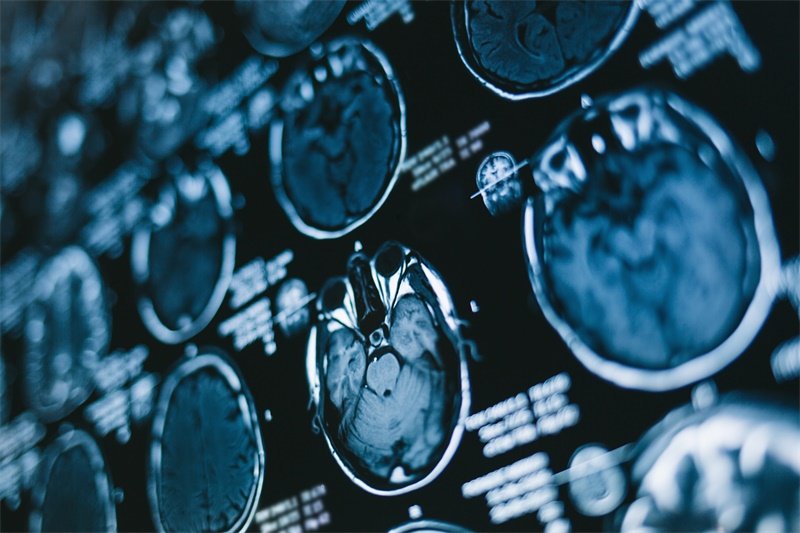

影像学检查

利用X线、CT、MRI等影像学检查,可以帮助医生评估肿瘤的大小和位置。这些检查能够清楚显示肿瘤与周围软组织的关系,为后续治疗提供重要依据。

在影像学检查中,MRI是最有效的工具,它可以详细地显示出肿瘤的结构特征及对神经组织的影响。同时,MRI无辐射,对患者的健康更为友好。